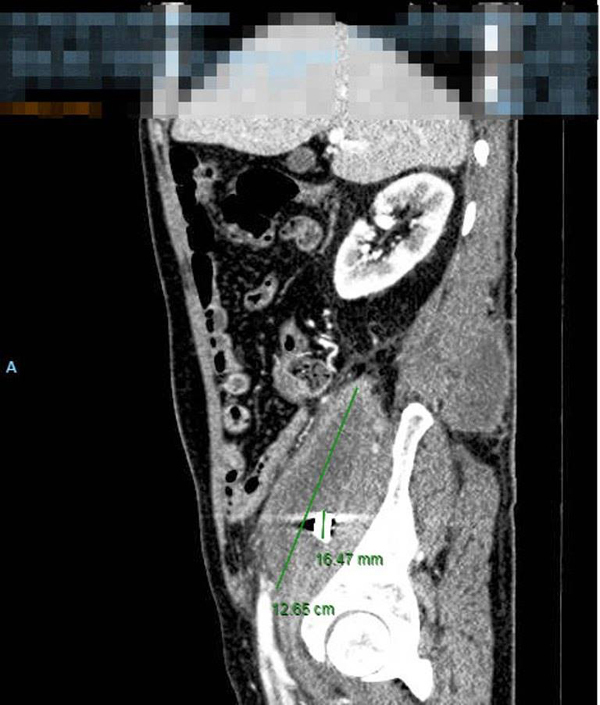

Khi nhập viện, bệnh nhân được thăm khám toàn diện, chụp cắt lớp điện toán. Kết quả kiểm tra phát hiện bệnh nhân có một ổ áp xe to tại vùng cơ thắt lưng chậu phải, ổ áp xe đã lan ra sau lưng. Hình ảnh chụp cho thấy, một mảnh kim loại giống mảnh đạn lúc khai thác bệnh sử.

Ảnh chụp CT ổ áp xe và viên đạn vẫn nằm suốt 40 năm trong ổ bụng bệnh nhân. Ảnh: BSCC

Sau khi cân nhắc, bác sĩ quyết định mổ lấy mảnh đạn ra khỏi ổ bụng cho bệnh nhân. Mảnh đạn với kích thước 1x1 (cm), nhiều cạnh sắc cuối cùng cũng được lấy ra sau nhiều giờ phẫu thuật.